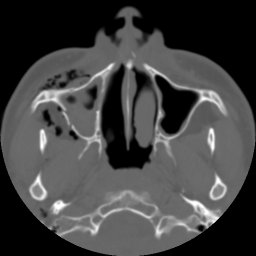

Return to Maxillary Sinus Fracture